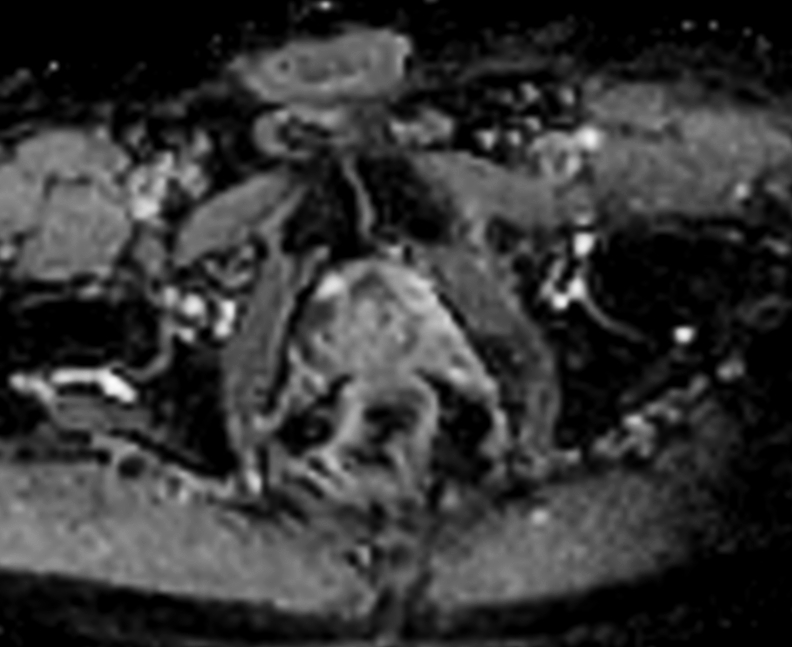

70-year-old male with prostate cancer, cT3bNxM, Gleason 6, PSA 7.9 mg/L, underwent MRI on Ingenia 3.0T MR-RT before radiation therapy, next to CT simulation. Patient was imaged at Ingenia MR-RT 3.0T using FlexCoverage Anterior Coil in combination with the integrated Posterior Coil.